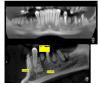

ден Опубликовано 26 октября, 2012 Автор Поделиться Опубликовано 26 октября, 2012 Неожиданное продолжение. Пришла томограмма, по описанию ставят Остеома или Цементома. Ясно что без гистологии не подтвердить.Вопрос: можно ли в опухоль ставить имплант? Глав.врач считает можно,ортопед тоже. Я думаю в стационар направить на удаление, заодно удалить ненужные зубы под общим наркозом. Ссылка на комментарий

Bier Опубликовано 26 октября, 2012 Поделиться Опубликовано 26 октября, 2012 Не трогайте и имплант туда не ставьте 1 Ссылка на комментарий

ден Опубликовано 26 октября, 2012 Автор Поделиться Опубликовано 26 октября, 2012 Bier Не силён в онкологии,но опухоль может дать рост (может она и растёт,пациент просто не знает). А если рядом ставить имплант, то как потом удалять опухоль если будет необходимость? Ссылка на комментарий

Bier Опубликовано 27 октября, 2012 Поделиться Опубликовано 27 октября, 2012 это цементома скорее всего. Махать скальпелем из-за нее не нужно. 1 Ссылка на комментарий